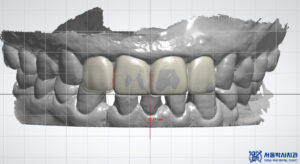

이렇게 MTA 신경치료로

앞니 자연치아를 잘 살린 이후에

원내 기공소에서 크라운

제작을 진행하였습니다.

본원 자체 운영 중인 원내기공소에서

1:1 개인 맞춤형으로

크라운을 제작하고 있습니다.

10년 차 이상의

치과기공사 실장님이 상주하며,

정교하고 세밀하게 디자인하여

보철물을 제작합니다.

또한 저작하는데 편하실 수 있도록

기능적인 면뿐만 아니라,

전체적으로 자연치아 모양과 색 등

자연스럽게 구현이 가능하도록

전문적으로 작업을 하고 있습니다.